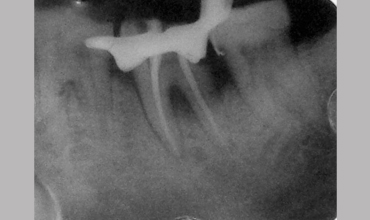

NON SURGICAL MANAGEMENT OF ENDODONTIC LESION AND SURGICAL MANAGEMENT OF PERIODONTIC LESION